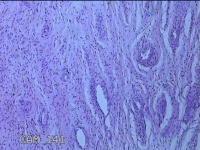

宫颈6点、12点组织

性别

女

年龄

33岁

临床诊断

人乳头瘤病毒感染

一般病史

发现HPV18,其他12种阳性近一月。

标本名称

大体所见

1.“宫颈6点组织”:灰白粉红色组织0.5x0.3x0.2cm一块。 2.“宫颈7点组织”:灰白暗红色组织0.8x0.3x0.2cm两块。

图1